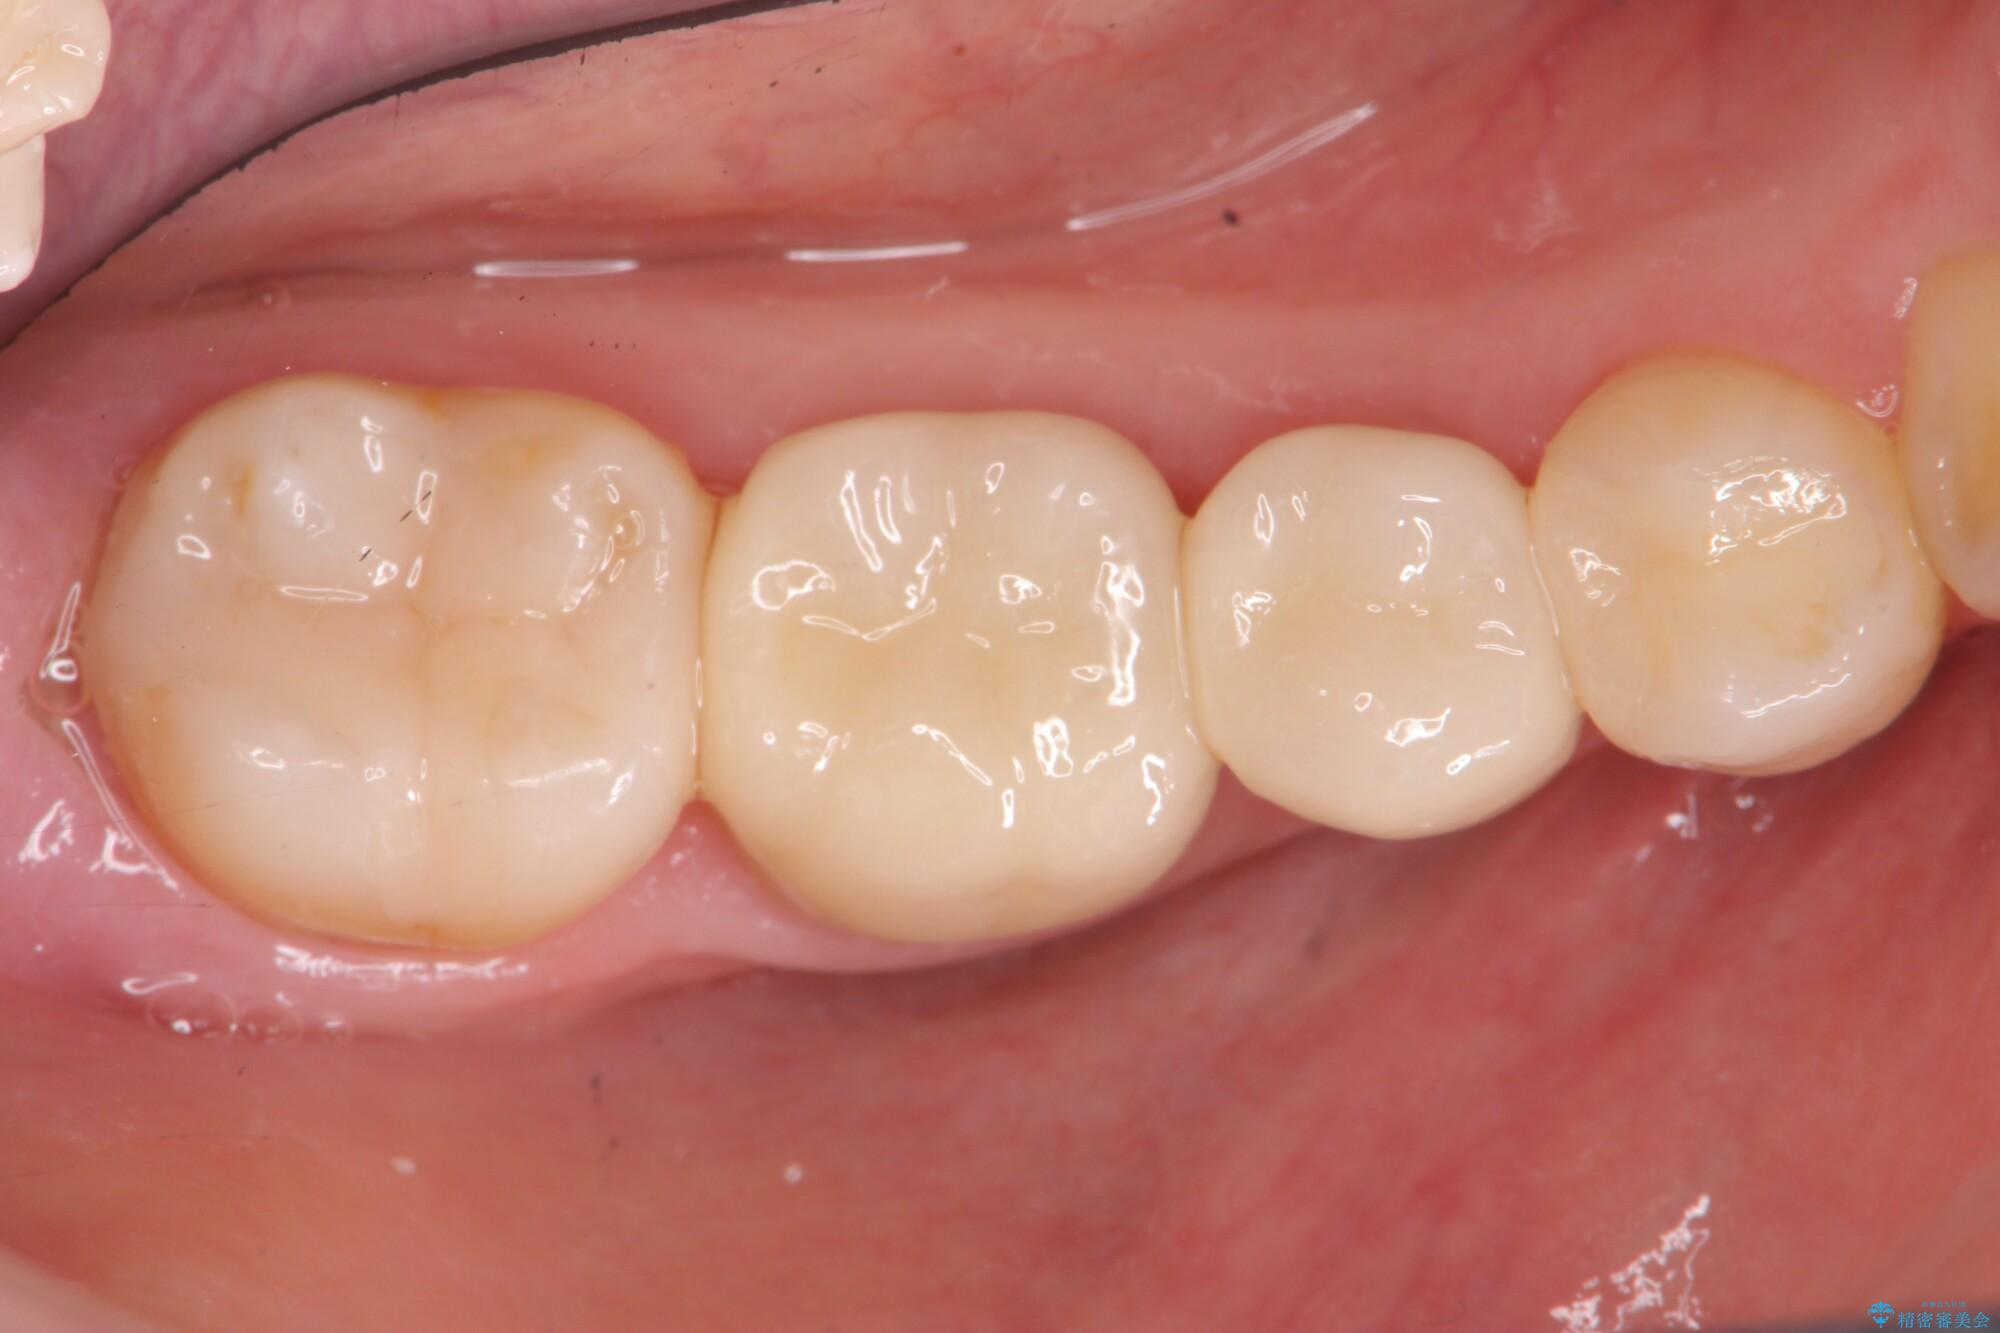

治療後について

歯ぐきの炎症も治まり、疼きなどの違和感もなくなりました。